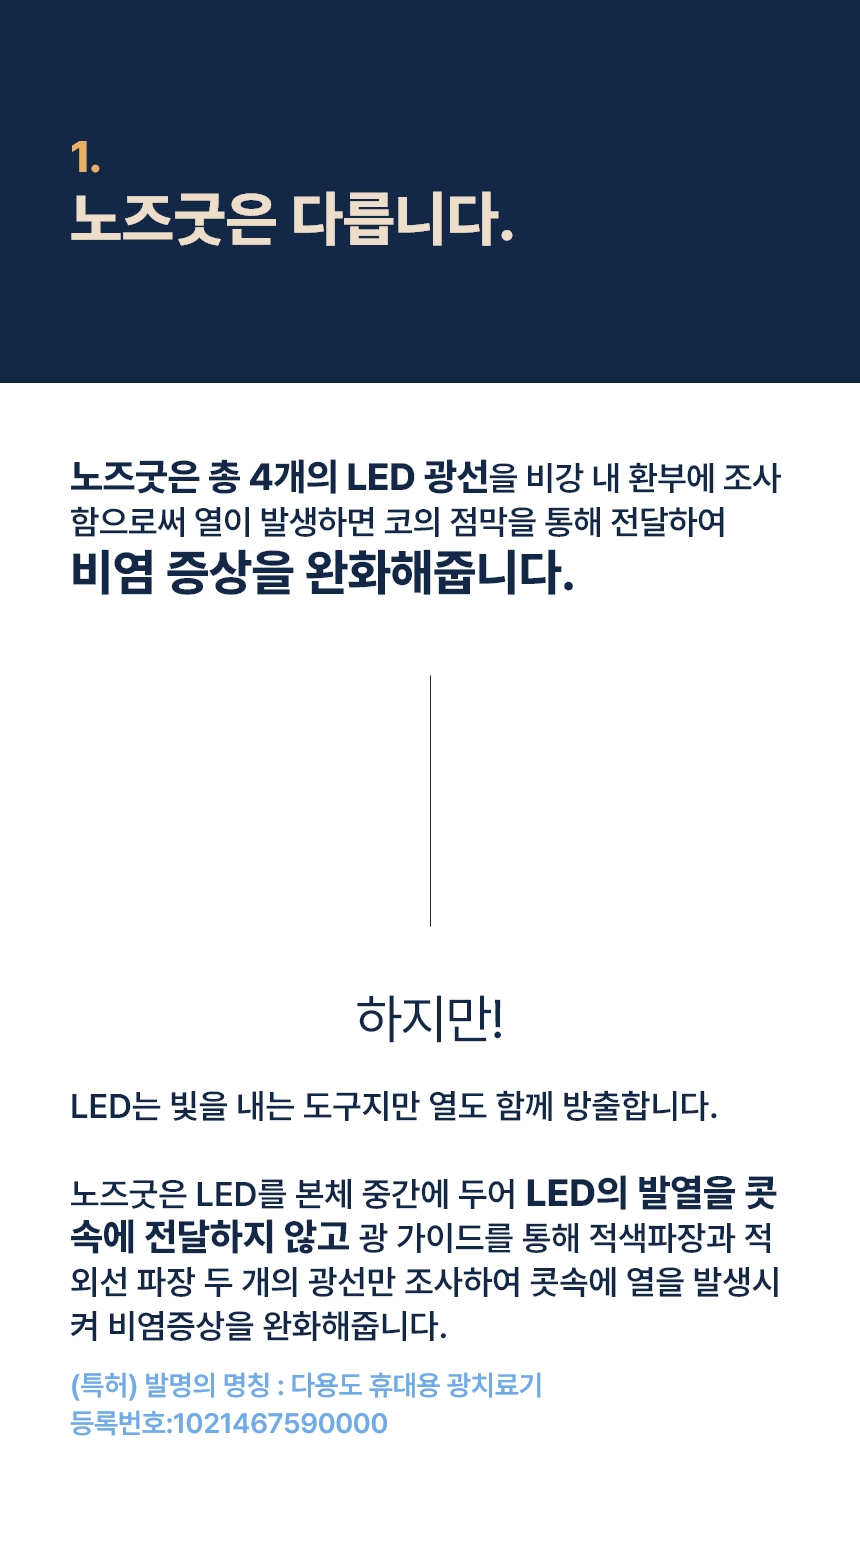

현재 특허 등록된 광 에미터 기술은 광 에미터(광가이드)를 이용해 LED를 외부에 두어 저항에 의한 발열을 콧속에 넣지않고, 비염에 도움이 되는 적색과 적외선 광선만 조사하는 방법입니다.

“LED는 빛도 나오지만 열도 나옵니다. 기기 끝에서 LED 빛이 나오면서 비강 점막을 건조시킨다는 부작용이 있었어요. 이를 개선하기 위해 무발열 광 에미터 기술을 적용했습니다. 광케이블처럼 LED 빛이 전파되는 통로를 만들어주는 방식이에요. 이비인후과에서 쓰는 광 치료기가 1세대, 기존 가정용 광치료기가 2세대라면 무 발열 광에미터 기술은 3세대라고 할 수 있죠.”